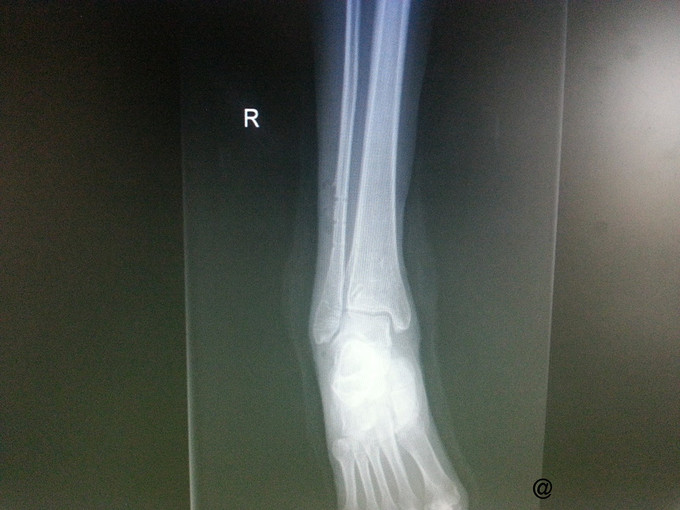

主诉:右三踝骨折ORIF术后一年半,要求取出内固定 病史:患者一年半前因外伤致右三踝骨折,1年前我院行“右三踝骨折ORIF术”。术顺,目前患者术后恢复良好,无切口处疼痛红肿热痛、无畸形愈合,为取出内固定再次入院。

查体:右侧外踝处可见一纵行8cm左右的陈旧性手术疤痕,愈合良好,踝关节无压痛,无肿胀,活动可。四肢肌力、肌张力正常。足趾自主活动良好,末梢血运正常,足背动脉搏动可及,皮肤感觉存在。其他肢体未见明显异常。 辅查:右侧踝关节正侧位片:右侧内外踝骨折内固定术后,内固定器在位,断端对位对线可。

诊断:取除骨折内固定装置(右三踝骨折术后) 处理:右踝关节骨折术后取内固定术